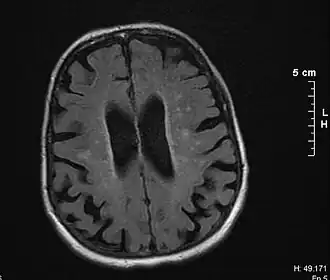

| Cérebro de vítima de demência vascular por leucoaraiose | |